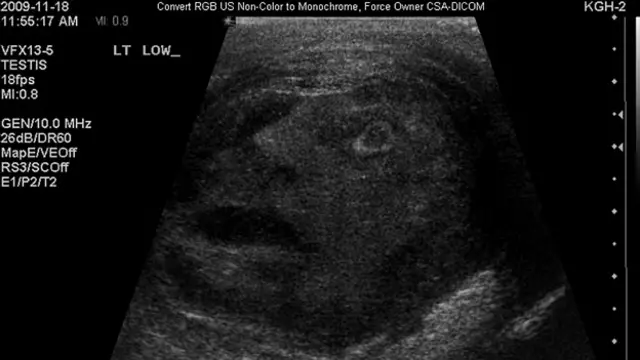

Один из самых странных случаев произошел с урологом Грегори Робертсом из канадского Кингстона. Представьте себе удивление его пациента, когда на экране УЗИ-аппарата появилось это лицо с открытым ртом, скрытое внутри его мошонки!

Автор фото, Gregory Roberts